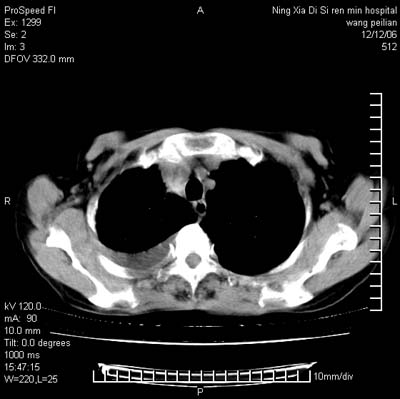

标题: CT5609:胸部:女77 病史不详 [打印本页]

标题: CT5609:胸部:女77 病史不详

两肺可见多个大小不等的结节,左侧有胸水,纵隔淋巴结增大,考虑是细支气管肺泡癌

两肺尖纤维索状影,两下肺结节块状影,且有钙化灶,右胸腔积液。考虑肺结核并胸膜炎。

两肺尖纤维索状影,两下肺结节块状影,且有钙化灶,右胸腔积液。考虑肺结核并胸膜炎肺间质纤维化

从图中见许多致密的结节影,增强后明显强化,考虑血管炎症肉芽肿.

从图中见许多致密的结节影,,增强后明显强化,考虑血管炎症肉芽肿.当然还有慢支并小叶中央型肺气肿以及陈旧结核,胸腔积液.

考虑:1、慢性支气管炎合并全小叶型肺气肿、间质纤维化;

2、双肺结核;

3、右侧胸膜炎(积液)。

双肺见多个结节状及条索状影,双侧胸腔积液,右侧叶间积液,考虑结核性胸膜炎